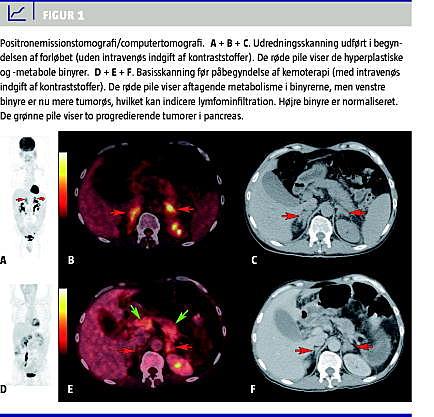

PET med lavdosis computertomografi (CT) foretaget på mistanke om paraneoplasi viste fokalt øget metabolisme i pancreas, duodenum og lymfeknuder i mesenteriet. Binyrerne var hyperplastiske med symmetrisk øget fluordeoxyglukose (FDG)-optagelse (Figur 1 A + B + C). Fundene blev tolket som tumorer i pancreas og duodenum med lymfeknudemetastaser i mesenteriet og ACTH-stimulation af binyrerne, da disse var hyperplastiske, men uden tumorpræg, som man ville forvente ved lymfominfiltration eller metastaser. Under udredningen for NET blev der udført octreotidskintigrafi, som viste normale forhold.

Årsagen til den adrenale hyperplasi og hypermetabolisme hos patienten i sygehistorien er uafklaret, men skyldes muligvis en non-ACTH-medieret stimulans, f.eks. cytokiner som foreslået af Jenkins et al . Dette ville forklare den normale binyrehormonsekretion. En ny PET/CT før behandling viste aftagende metabolisme i binyrerne, men patienten var sat i behandling med højdosis-prednisolon tre dage forinden (Figur 1D + E + F). Højre binyre var nu normaliseret, mens venstre binyre var tiltagende tumorpræget, hvilket talte for lymfominfiltration.